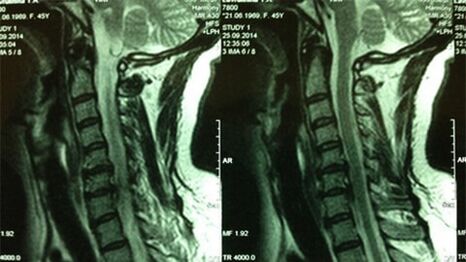

- X -Ray of the cervical department;In the initial phase of the process, the MRI of the cervical department will be more informative - will provide high -quality solid and soft tissue visualization - will indicate the state of the intervertebral discs, the presence of osteophytes, deformities, damage to the nerve roots and blood vessels;will evaluate the condition of ligaments, muscles, bone tissue;